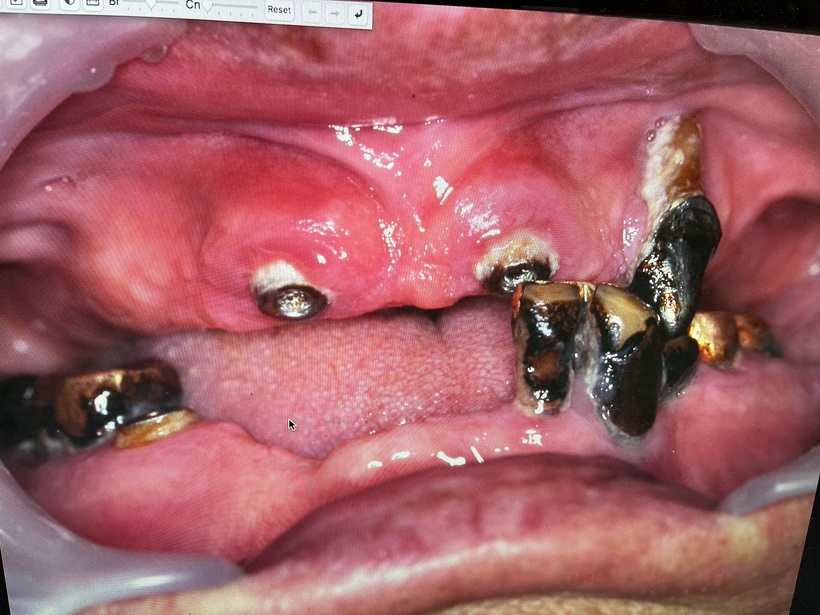

初診時 虫歯・歯周病・清掃不良

治療の結果上下で10本が残りました。上顎は2本の歯を総義歯の中に組み込みました。下顎のコーヌスブリッジ義歯 8本の支台歯(実際は7本ですが右下6番は根を2つに分割して使用しています)で14本の歯を作りました。

80歳から96歳まで16年間拝見しました。16年間で失った歯は亡くなる直前に0.5本でした。歯周病・糖尿病・癌の状態もよく最後は自宅で亡くなりました。歯周病と糖尿病と癌はお友達疾患であり、歯周病の状態が改善すれば悪い友達も寄り付かなくなります。